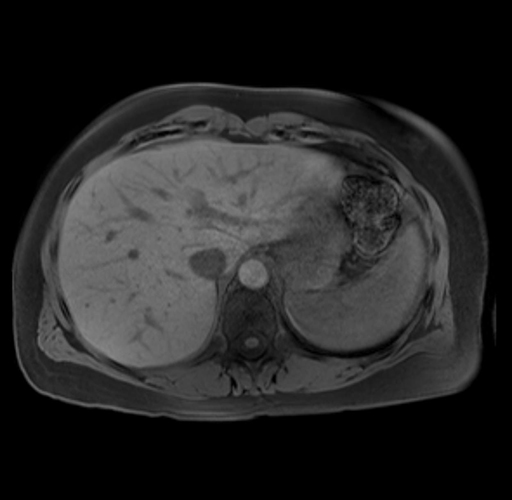

Imaging Analysis

Look through the patient's CT scan to identify any areas of concern for the necessary procedure.

Based on your CT findings, which issue(s) are present and would give reason for "planned slowing down moment(s)" in this case?